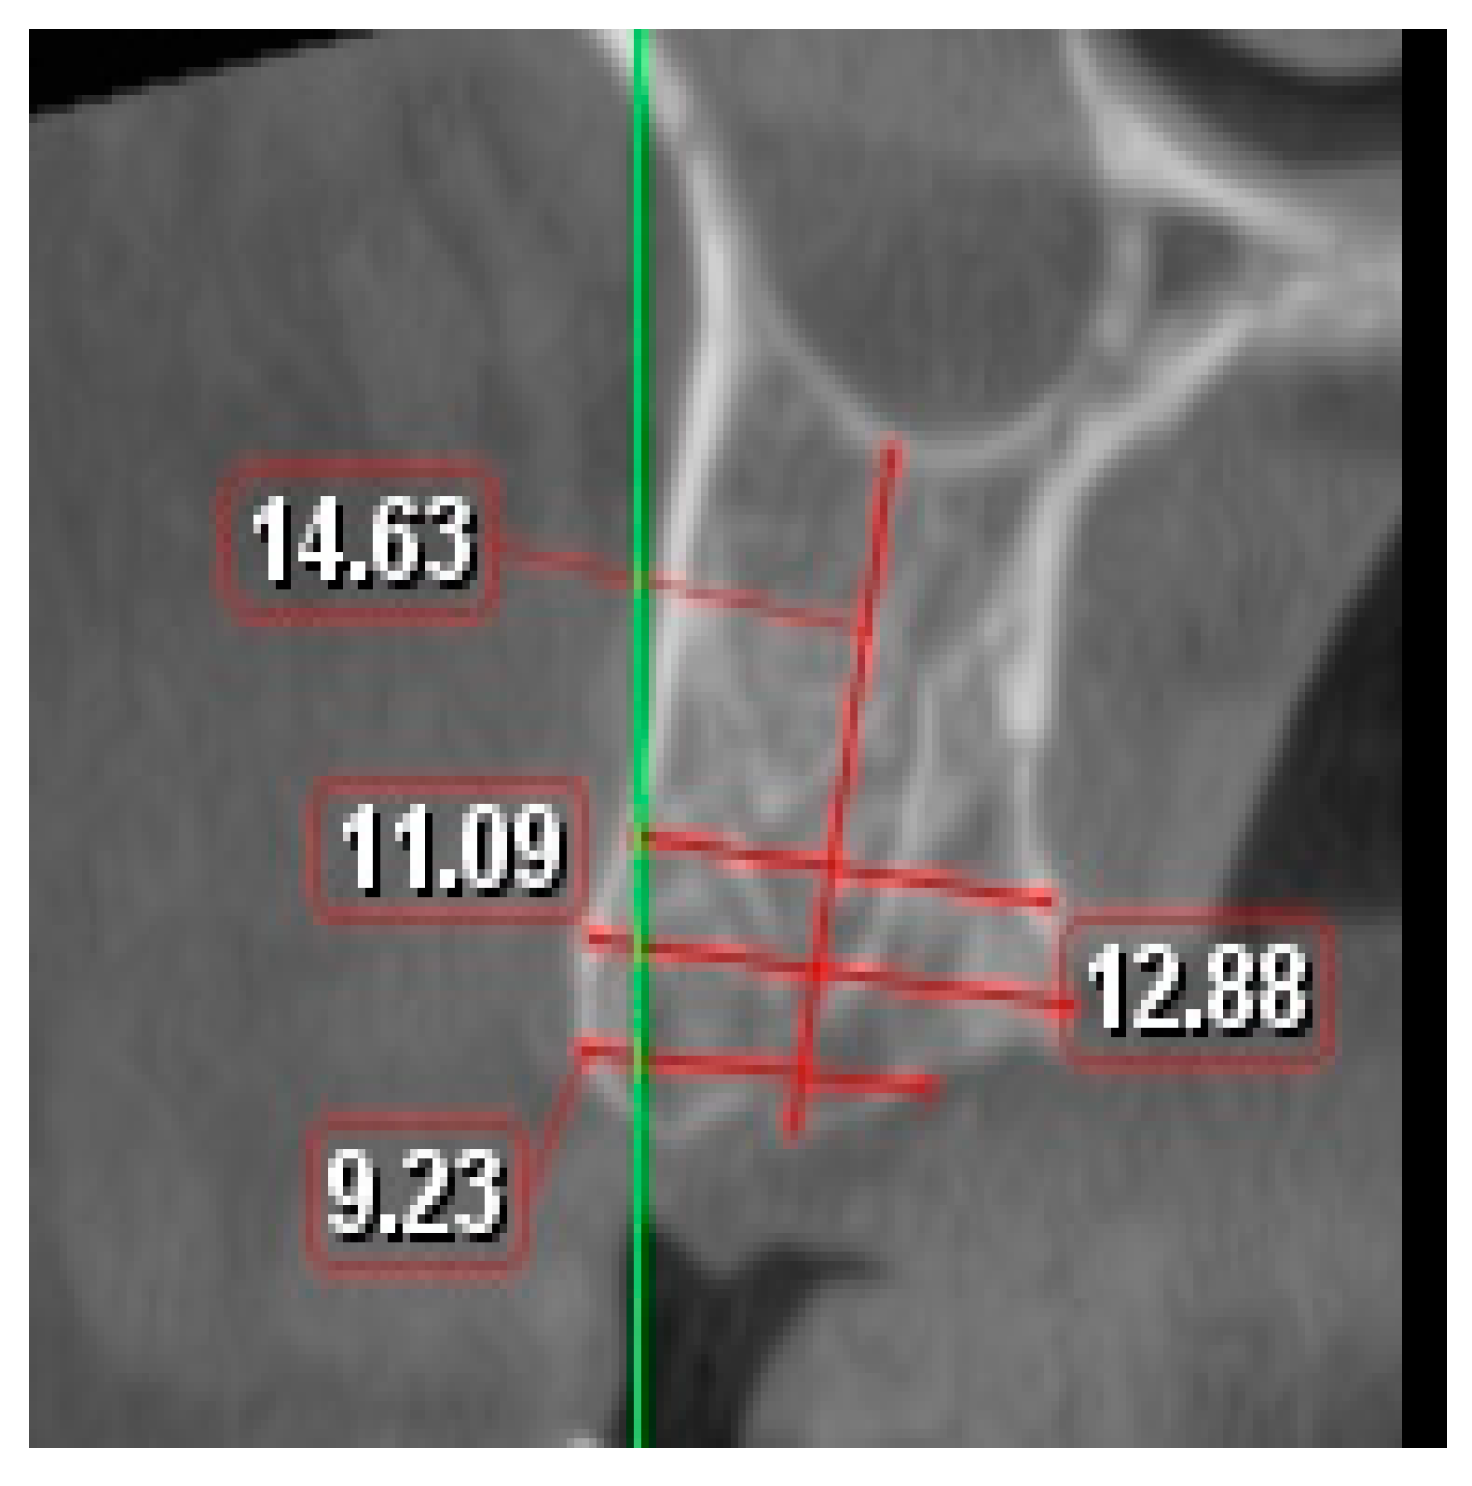

The two images were superimposed manually using specialized software (OnDemand3D, Cybermed Inc., Daejeon, Republic of Korea) [35] while using two adjacent anatomical structures as fixed landmarks. Using linear measurement tools, the width of the socket was measured at three different distances of 1, 3, and 5 mm from the most coronal point of the bone crest, and the length of the socket was measured from the bone crest to the sinus floor (Figure 1). The analysis was conducted in central and proximal sites following a 45°-degree orientation at the axis of the tooth as a reference.

Figure 1.

Method for measurement from the CBCT.